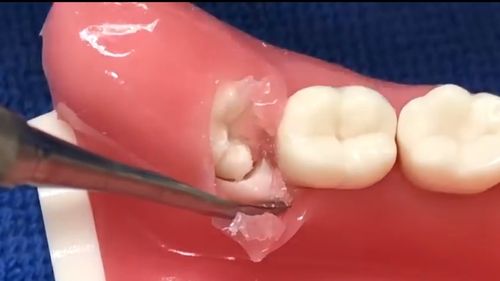

【图】智齿拔除术切口的类型